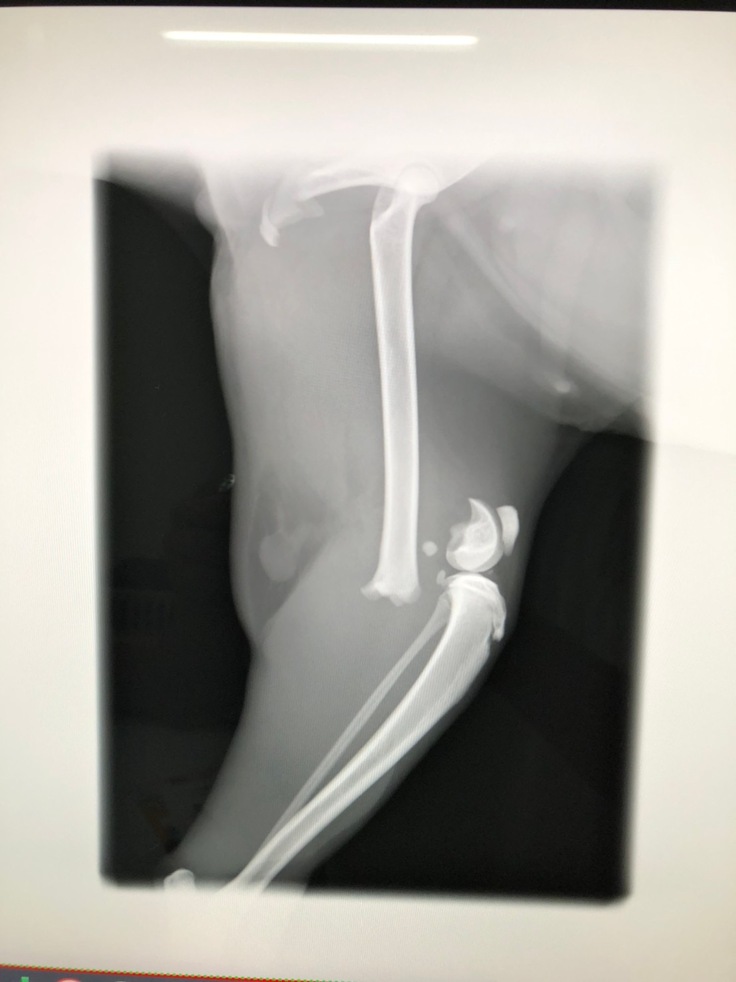

左大腿骨遠位骨端板骨折のレントゲン

左大腿骨遠位骨端板骨折の手術、子宮卵巣摘出手術・検査・入院代 300,000円

左大腿骨遠位骨端板骨折に対してクロスピン固定、子宮卵巣摘出手術